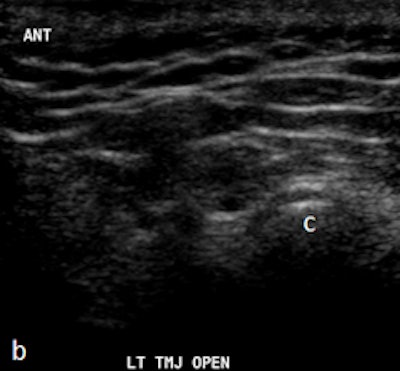

Dr. Friedman prefers that patients be supine on a stretcher with the jaw tilted away from the side to be examined. Then the person performing the ultrasound palpates the joint while the patient opens and closes her mouth. Gel is then placed on the joint, and the probe is placed at various positions around the joint. The images are examined to determine whether there is anterior displacement of the disk while the joint is the closed-mouth position.